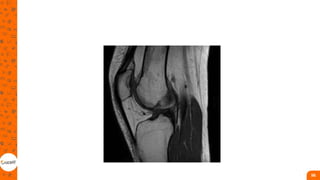

• Fratura ao redor do joelho

• Podem estar localizadas na região distal do

fêmur, na patela ou no platô tibial;

• São causadas por traumas de baixa

energia na população geriátrica e alta

energia na população jovem;

• O fêmur distal e o platô tibial são regiões

próximas às estruturas neurovasculares e

as lesões de nervos, sobretudo do nervo

fibular;

• As fraturas por luxações também são

comuns em traumas de alto impacto. Nas

fraturas da patela, pode ocorrer lesão do

mecanismo extensor

Fratura ao redor do joelho

• Grande morbidade;

• Geralmente cirúrgico;

• reconstrução anatômica da

superfície articular, reparo dos

tecidos moles lesionados,

restauração do eixo, congruência

e estabilidade articular. Nas

fraturas distais do fêmur, o

tratamento padrão é a redução

aberta e a fixação interna.

• O tratamento conservador

somente em fraturas impactadas,

não desviadas e extra-

articulares, ou em pacientes

considerados inoperáveis e não

deambuladores.